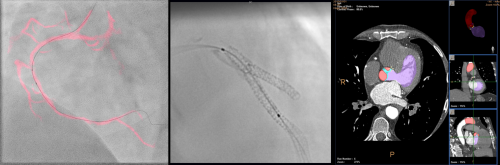

´ë±¸°¡Å縯´ëÇб³º´¿øÀº Çʸ³½ºÀÇ ÃÖ½ÅÇü Ç÷°üÁ¶¿µÁø´Ü±â±â ¾ÆÁÖ¸®¿Â(Azurion 7M12)À» ÃÖ±Ù µµÀÔÇÏ¿© ½ÉÇ÷°üÃÔ¿µ½Ç¿¡¼­ ¿î¿ëÁßÀ̶ó°í 2¿ù 14ÀÏ(±Ý) ÀüÇß´Ù.

¾ÆÁÖ¸®¿ÂÀº Ç÷°ü ¹× ±¸Á¶Àû ½ÉÁúȯÀ» Áø´ÜÇϰí ÁßÀç½Ã¼úÀ» Çϴµ¥ ¾²ÀÌ´Â Smart PRO Ç÷§Æû ±â¹ÝÀÇ ÃÊÁ¤¹Ð ÃÖ÷´Ü ±â±â·Î ¿©·¯ °¡Áö ÀåÁ¡ÀÌ ÀÖ´Ù.

ÃֽеðÁöÅÐ ¿µ»ó ±â¼úÀ» Àû¿ëÇÏ¿© °íÇØ»óµµ ¿µ»óÀ¸·Î ÀÇ·áÁøÀÌ ¹Ì¼Ò º´º¯À» ºñ·ÔÇØ Ç÷°ü ÁúȯÀ» È¿°úÀûÀ¸·Î Áø´ÜÇÒ ¼ö ÀÖ°ÔÇϴµ¥ ÁßÀçÀû ½Ã¼ú ½Ã ¹Ì¼Ò º´º¯À» È®ÀÎÇÔÀ¸·Î½á º¸´Ù Á¤È®ÇÑ Ä¡·á°¡ °¡´ÉÇÏ´Ù. ƯÈ÷ 12ÀÎÄ¡ µðÅØÅÍ´Â ½ÉÇ÷°ü ÁßÀç½Ã¼ú ½Ã º¸´Ù ³ÐÀº Áø´Ü¿µ¿ªÀ» º¼ ¼ö ÀÖ¾î È¿°úÀûÀÎ ÇØºÎÇÐÀû Áø´ÜÀ» °¡´ÉÄÉ ÇÑ´Ù.

▴µ¿Àû °ü»óµ¿¸Æ ·Îµå¸Ê(Dynamic Coronary Roadmap) ▴½ºÅÙÆ®ºÎ½ºÆ®(StentBoost)▴ÇÏÆ® ³×ºñ°ÔÀÌÅÍ(Heart Navigator)

¾Æ¿ï·¯, ÁßÀçÀû ½Ã¼ú Áß ½Ç½Ã°£À¸·Î °ü»óµ¿¸ÆÀÇ °æ·Î¸¦ ¾È³»ÇÏ¿© ½Ã¼úÀÇ Á¤È®¼º°ú ¾ÈÀü¼ºÀ» ³ôÀÌ´Â ±â¼úÀÎ µ¿Àû °ü»óµ¿¸Æ ·Îµå¸ÊÀÌ Å¾ÀçµÇ¾î ÀÖ¾î ½Ã¼úÀ» ºü¸£°í ¿ëÀÌÇÏ°Ô ÇÒ ¼ö ÀÖµµ·Ï ÇØ ÁØ´Ù. ½ºÅÙÆ® ¿µ»óÀ» ¼±¸íÇÏ°Ô Áõ°­½ÃŰ´Â ½ºÅÙÆ®ºÎ½ºÆ®´Â Á¤È®ÇÑ À§Ä¡¿¡ ½ºÅÙÆ® ½Ã¼úÀ» Çϵµ·Ï µµ¿òÀ» ÁØ´Ù.

¶ÇÇÑ, ¹Ì¸® ÃÔ¿µÇÑ ´Ù¸¥ ¿µ»óÀ» ½Ã¼ú ¿µ»ó¿¡ ¹Ý¿µÇÏ¿© ºñ±³Çϸ鼭 º¸°Å³ª °ãÃļ­ º¼ ¼ö ÀÖ´Â ½Ç½Ã°£ ¶óÀÌºê ¿µ»ó±â¼úÀº Á¶¿µÁ¦ »ç¿ë·®À» ÁÙÀ̸鼭 º¹ÀâÇÏ°í ¾î·Á¿î ½ÉÀåÇ÷°ü ¹× ÆÇ¸·Áúȯ, ¼±Ãµ¼º ½ÉÁúȯ µîÀÇ ±¸Á¶Àû ½ÉÁúȯ Ä¡·á¿¡ ¼º°øÀûÀÎ ½Ã¼úÀÌ °¡´ÉÇϵµ·Ï µµ¿ÍÁØ´Ù.

¹æ»ç¼±·® Àú°¨ ±â¼úÀΠŬ·¡·¯Æ¼(Clarity) IQ ±â¼úÀ» ÅëÇØ ¹æ»ç¼± ÇÇÆø·®À» 50~85% ÁÙÀ̸鼭µµ °íǰÁúÀÇ ¿µ»óÀ» ¾òÀ» ¼ö Àִµ¥ ÀÌ·¯ÇÑ ±â¼úÀº ÀÇ·áÁøµéÀÇ Áø´Ü ¹× Ä¡·á¿¡ ´ëÇÑ Á¤È®¼ºÀ» ´õ¿í Çâ»ó½ÃÄÑ ÁÖ¸ç, ȯÀÚµéÀÇ ¹æ»ç¼± ÇÇÆø ¹× ÇÕº´ÁõÀ» ÁÙÀÌ´Â ¾ÈÀü Á¦°í È¿°úµµ ÀÖ´Ù.